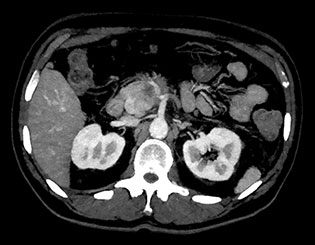

Widok obszaru anatomicznego uzyskany z użyciem różnych wyników spektralnych.

Obraz MonoE

Na tym zdjęciu pokazano zsyntetyzowany obraz monoenergetyczny uzyskany przy wstępnie ustawionej wartości keV.

MonoE